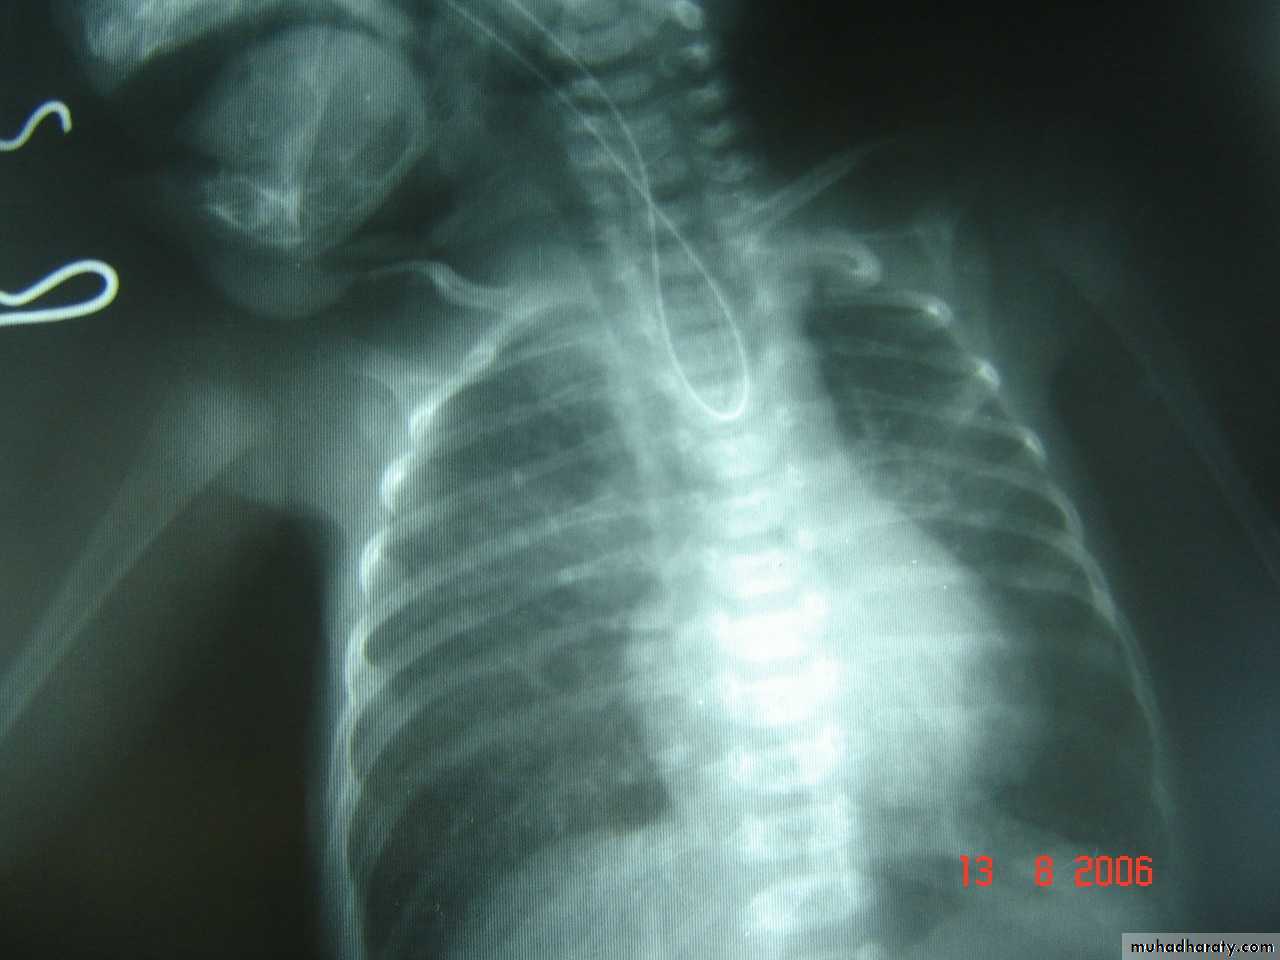

Second photo:

Diagnosis: congenital diaphragmatic hernia

Description: more dextrocardia – diaphragm not present – there is nasogastric tube

severe distress – very tired - 1 day age baby – more number of intestinal loops in

the chest - there is no lung tissue in the chest.

Treatment: pull the intestine ad close the hernia (through abdominal approach).